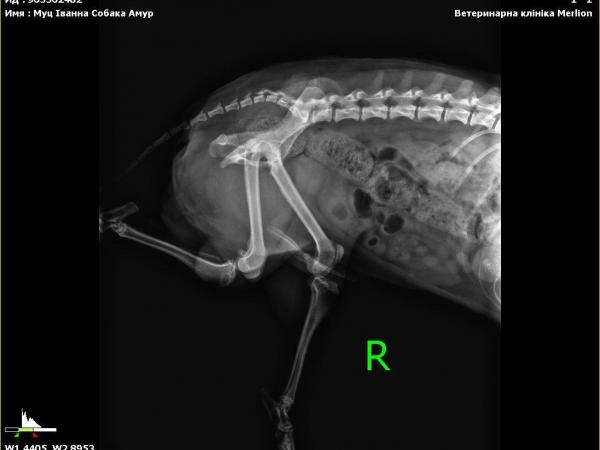

In der Klinik stellte sich heraus, dass Gucio etwa 3 Jahre alt ist und eine gebrochene Beckenregion hat. Wahrscheinlich wurde er von einem Auto angefahren. Deshalb konnte er sich nicht bewegen und lag an einer stark befahrenen Straße — ohne jede Chance, wenn niemand angehalten hätte.

Er erhielt erste tierärztliche Hilfe — Untersuchung, Impfung, Entwurmung. Sein Zustand wurde als schwer eingestuft: starke Unterkühlung, Erschöpfung und eine Verletzung, die eine langfristige Behandlung und Rehabilitation erfordert.